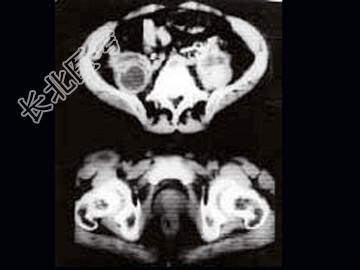

- 单项选择题女,34岁, 咳嗽,腰背疼痛二年, CT检查如图,最可能的诊断是 ( )

A、结核性脓肿

B、囊肿

C、淋巴管瘤

D、卵巢囊肿

E、卵巢囊腺瘤